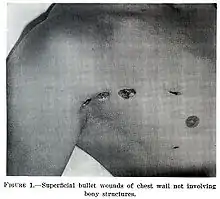

Tórax

La mayoría de las lesiones son heridas en el tórax y tienen una tasa de mortalidad (tasa de muerte) de menos del 10 %.[11] El traumatismo torácico penetrante puede dañar órganos vitales como el corazón y los pulmones y puede interferir con la respiración y la circulación. Las lesiones pulmonares que pueden ser causadas por un traumatismo penetrante incluyen laceración pulmonar (corte o desgarro), contusión pulmonar (moretón), hemotórax (una acumulación de sangre en la cavidad del pecho fuera del pulmón), neumotórax (una acumulación de aire en la cavidad del pecho) y hemoneumotórax (acumulación de sangre y aire). La succión del traumatismo torácico y la tensión del neumotórax puede resultar.